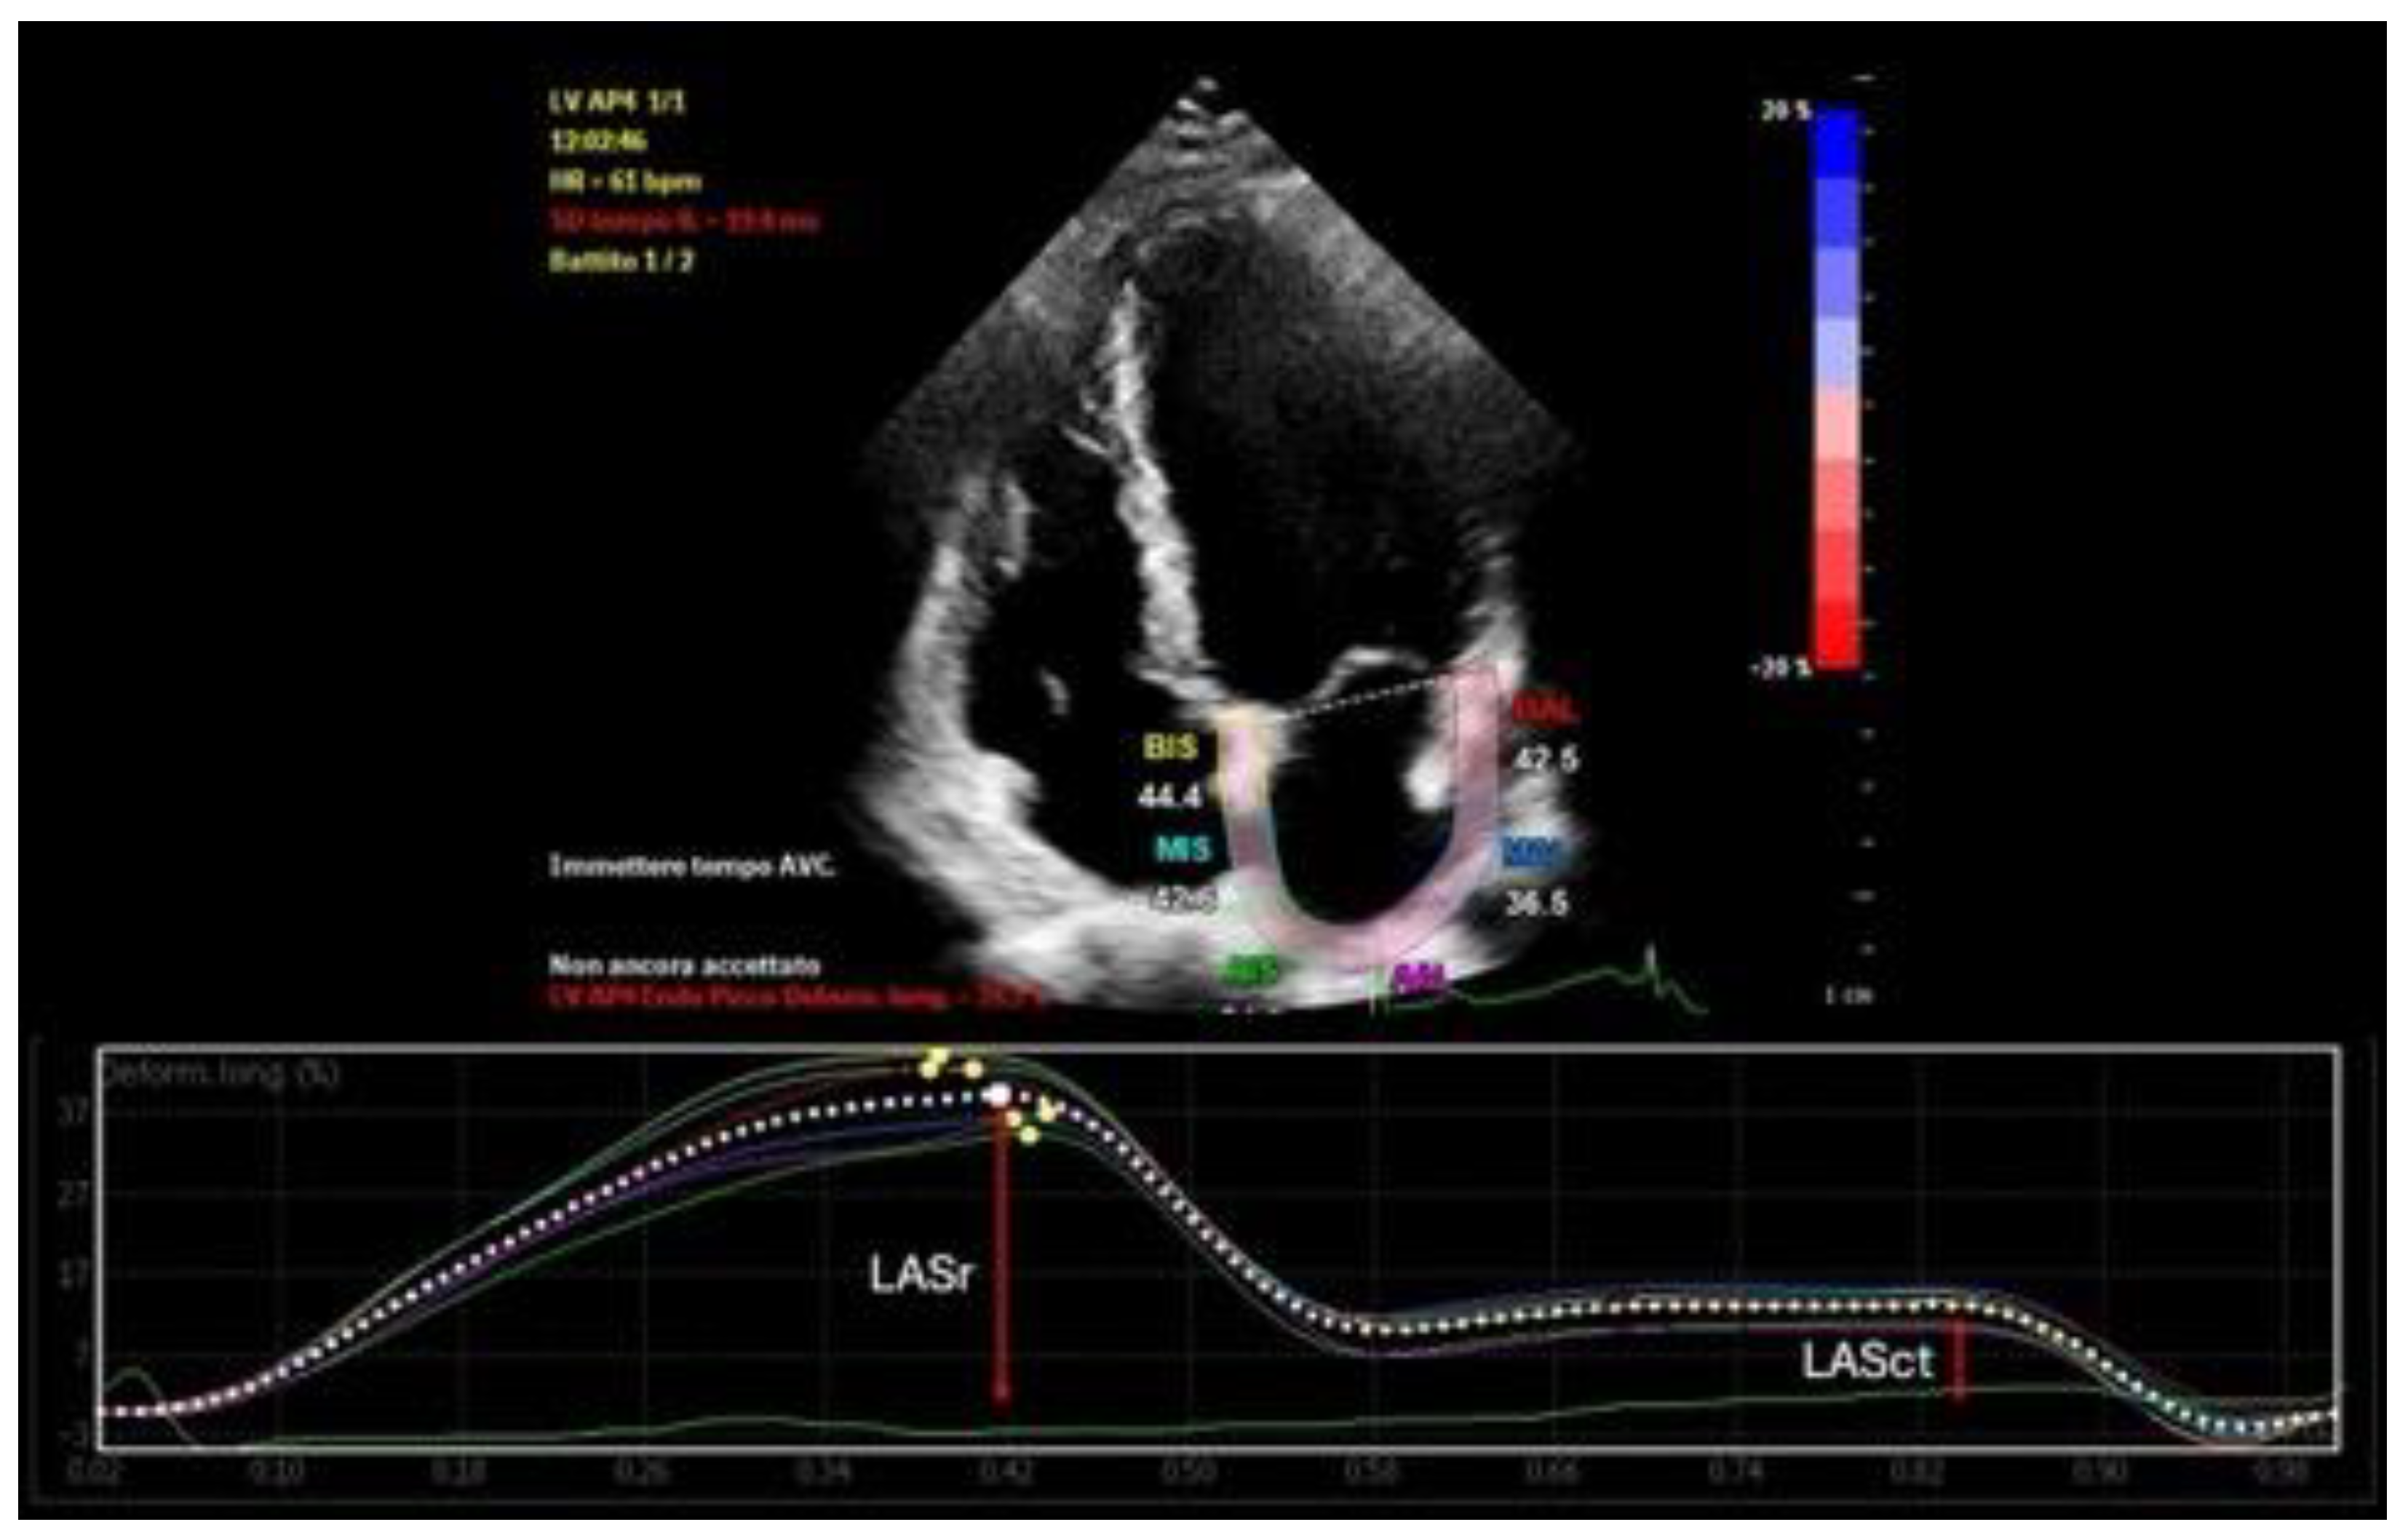

- Left Atrial Reservoir Strain (LASr): LASr is a measure of atrial deformation during ventricular systole, reflecting the reservoir function of the left atrium [19]. It is assessed using 2D speckle-tracking echocardiography and reported as a percentage (Figure 1). A normal LASr value is typically greater than 23%, indicating good atrial compliance and minimal fibrosis. Values between 15% and 23% are considered borderline, while values below 15% suggest advanced atrial remodeling [20]. Reduced LASr has been associated with atrial fibrosis, decreased left atrial compliance, and a higher risk of recurrence after catheter ablation [21].

- Left Atrial Contractile Strain (LASct): LASct represents the active contraction function of the left atrium and is evaluated using speckle-tracking echocardiography during the late diastolic phase [32] (Figure 1). It is measurable only in patients who are in sinus rhythm at the time of examination. Normal values are typically above 6%, whereas values below this threshold suggest poor contractile function and advanced atrial disease [33]. Impaired LASct has been linked to a greater likelihood of arrhythmia recurrence and reflects the diminished booster pump contribution of the atrium to left ventricular filling [34].